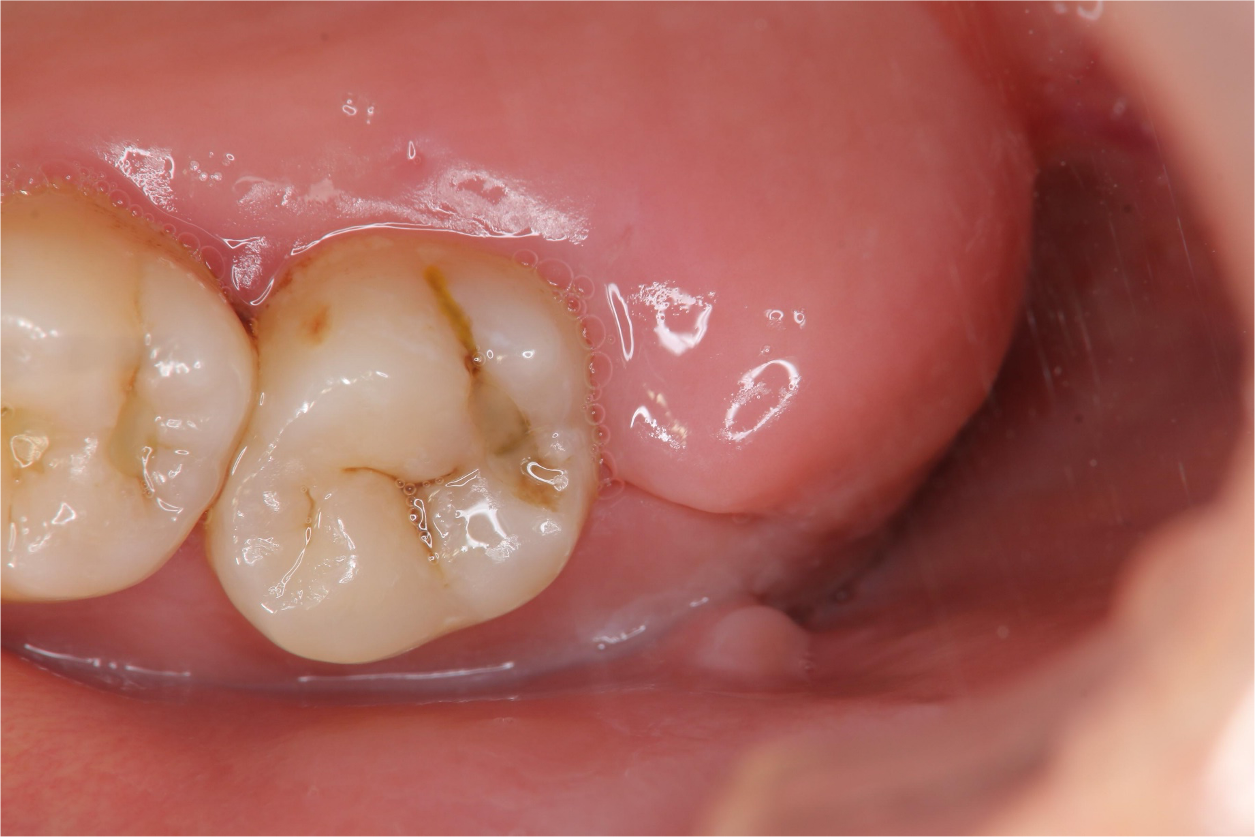

以水雷射切割皮瓣止血、再以手機等拔除阻生齒,並縫合之

1週後傷口癒合良好